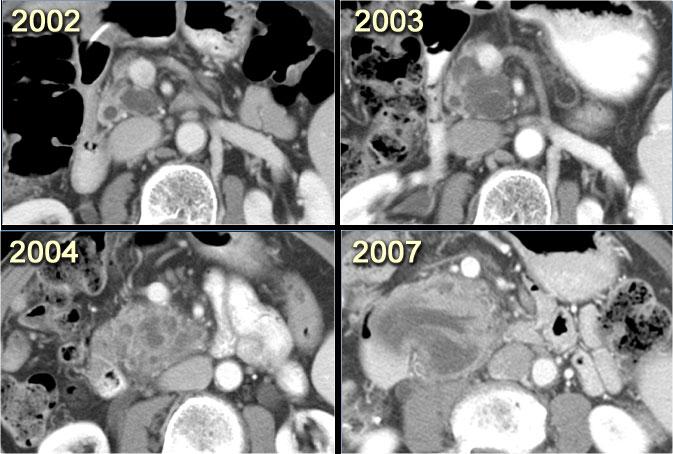

Hình ảnh CT của một bệnh nhân IPMN thể ống nhánh từ chối phẫu thuật.

Theo thời gian, u phát triển to hơn kèm giãn ống tụy chính, gợi ý biến đổi ác tính.

Đôi khi phải mất 5-8 năm mới quan sát thấy sự biến đổi này.